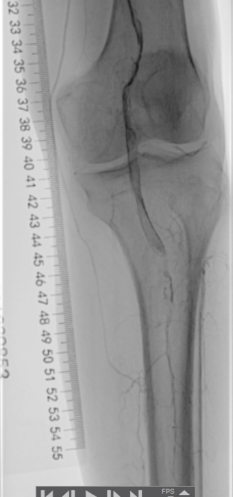

▲腘动脉可见充盈缺损

▲膝下主干动脉未见显影